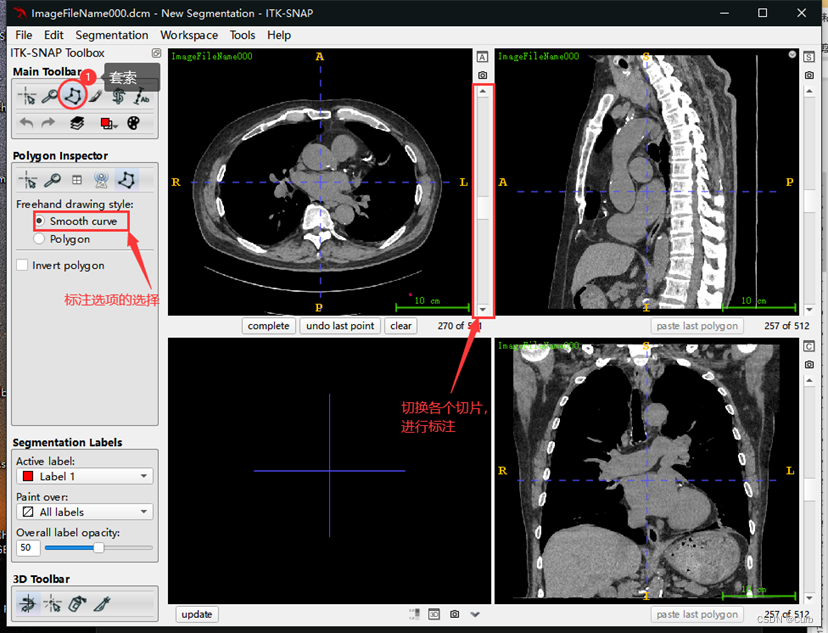

标注方法一:套索标注

套索标注有两个选项,Smooth和Polygon,推荐选用Smooth来进行拖动鼠标画取消,Polygon为给定关键点生成折线比较糙一些。画好外圈轮廓之后点击回车即可生成标注。选用一个方向的轴向图标注即可。

根据上图,选择好标注工具后,通过切换切片一张一张地进行标注(也可以通过滚动鼠标来切换),使用套索标注的例子(下面是放大之后的效果):

标注过程中,有两种方式,一种是通过长按鼠标左键进行标注;一种是通过不断单击鼠标左键进行标注。(具体感受一下就知道了)

对不同部位使用不同的标签,点击上图中的圈出位置,进行切换标签(颜色不同)。标注之后的效果如下: